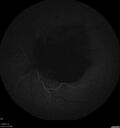

Hydroxychloroquine Toxicity86 views60 year old female received 6.5 mg/kg Plaquenil for 15 years and developed toxicity. VA 20/40 OD, 20/20 OSDec 22, 2024